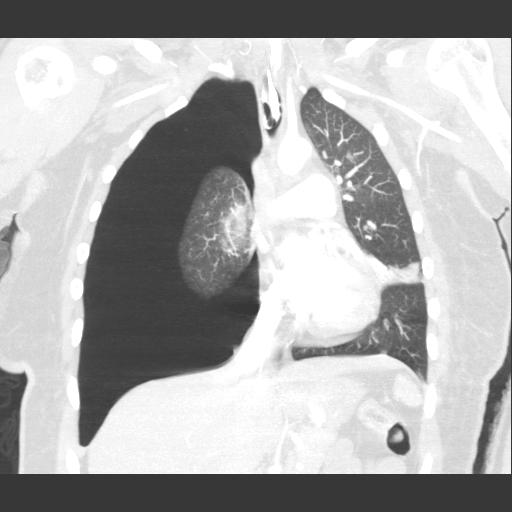

Traumatic Pneumothorax

Next, is a procedure needed at all?

- Conservative / Non-operative Management is appropriate for:

- Stable patient with no evidence of respiratory distress.

- Small pneumothoraces (some have said up to 20%, but no good pediatric studies that define a predictive volume).